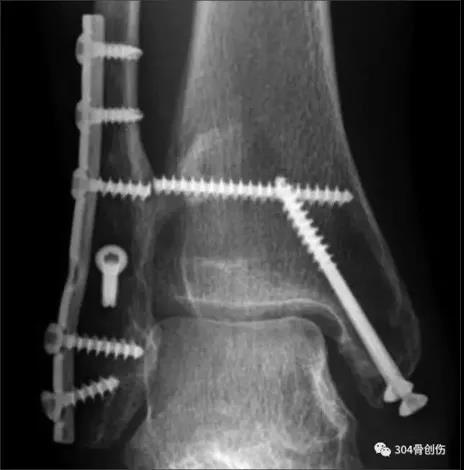

术后DR

术前DR